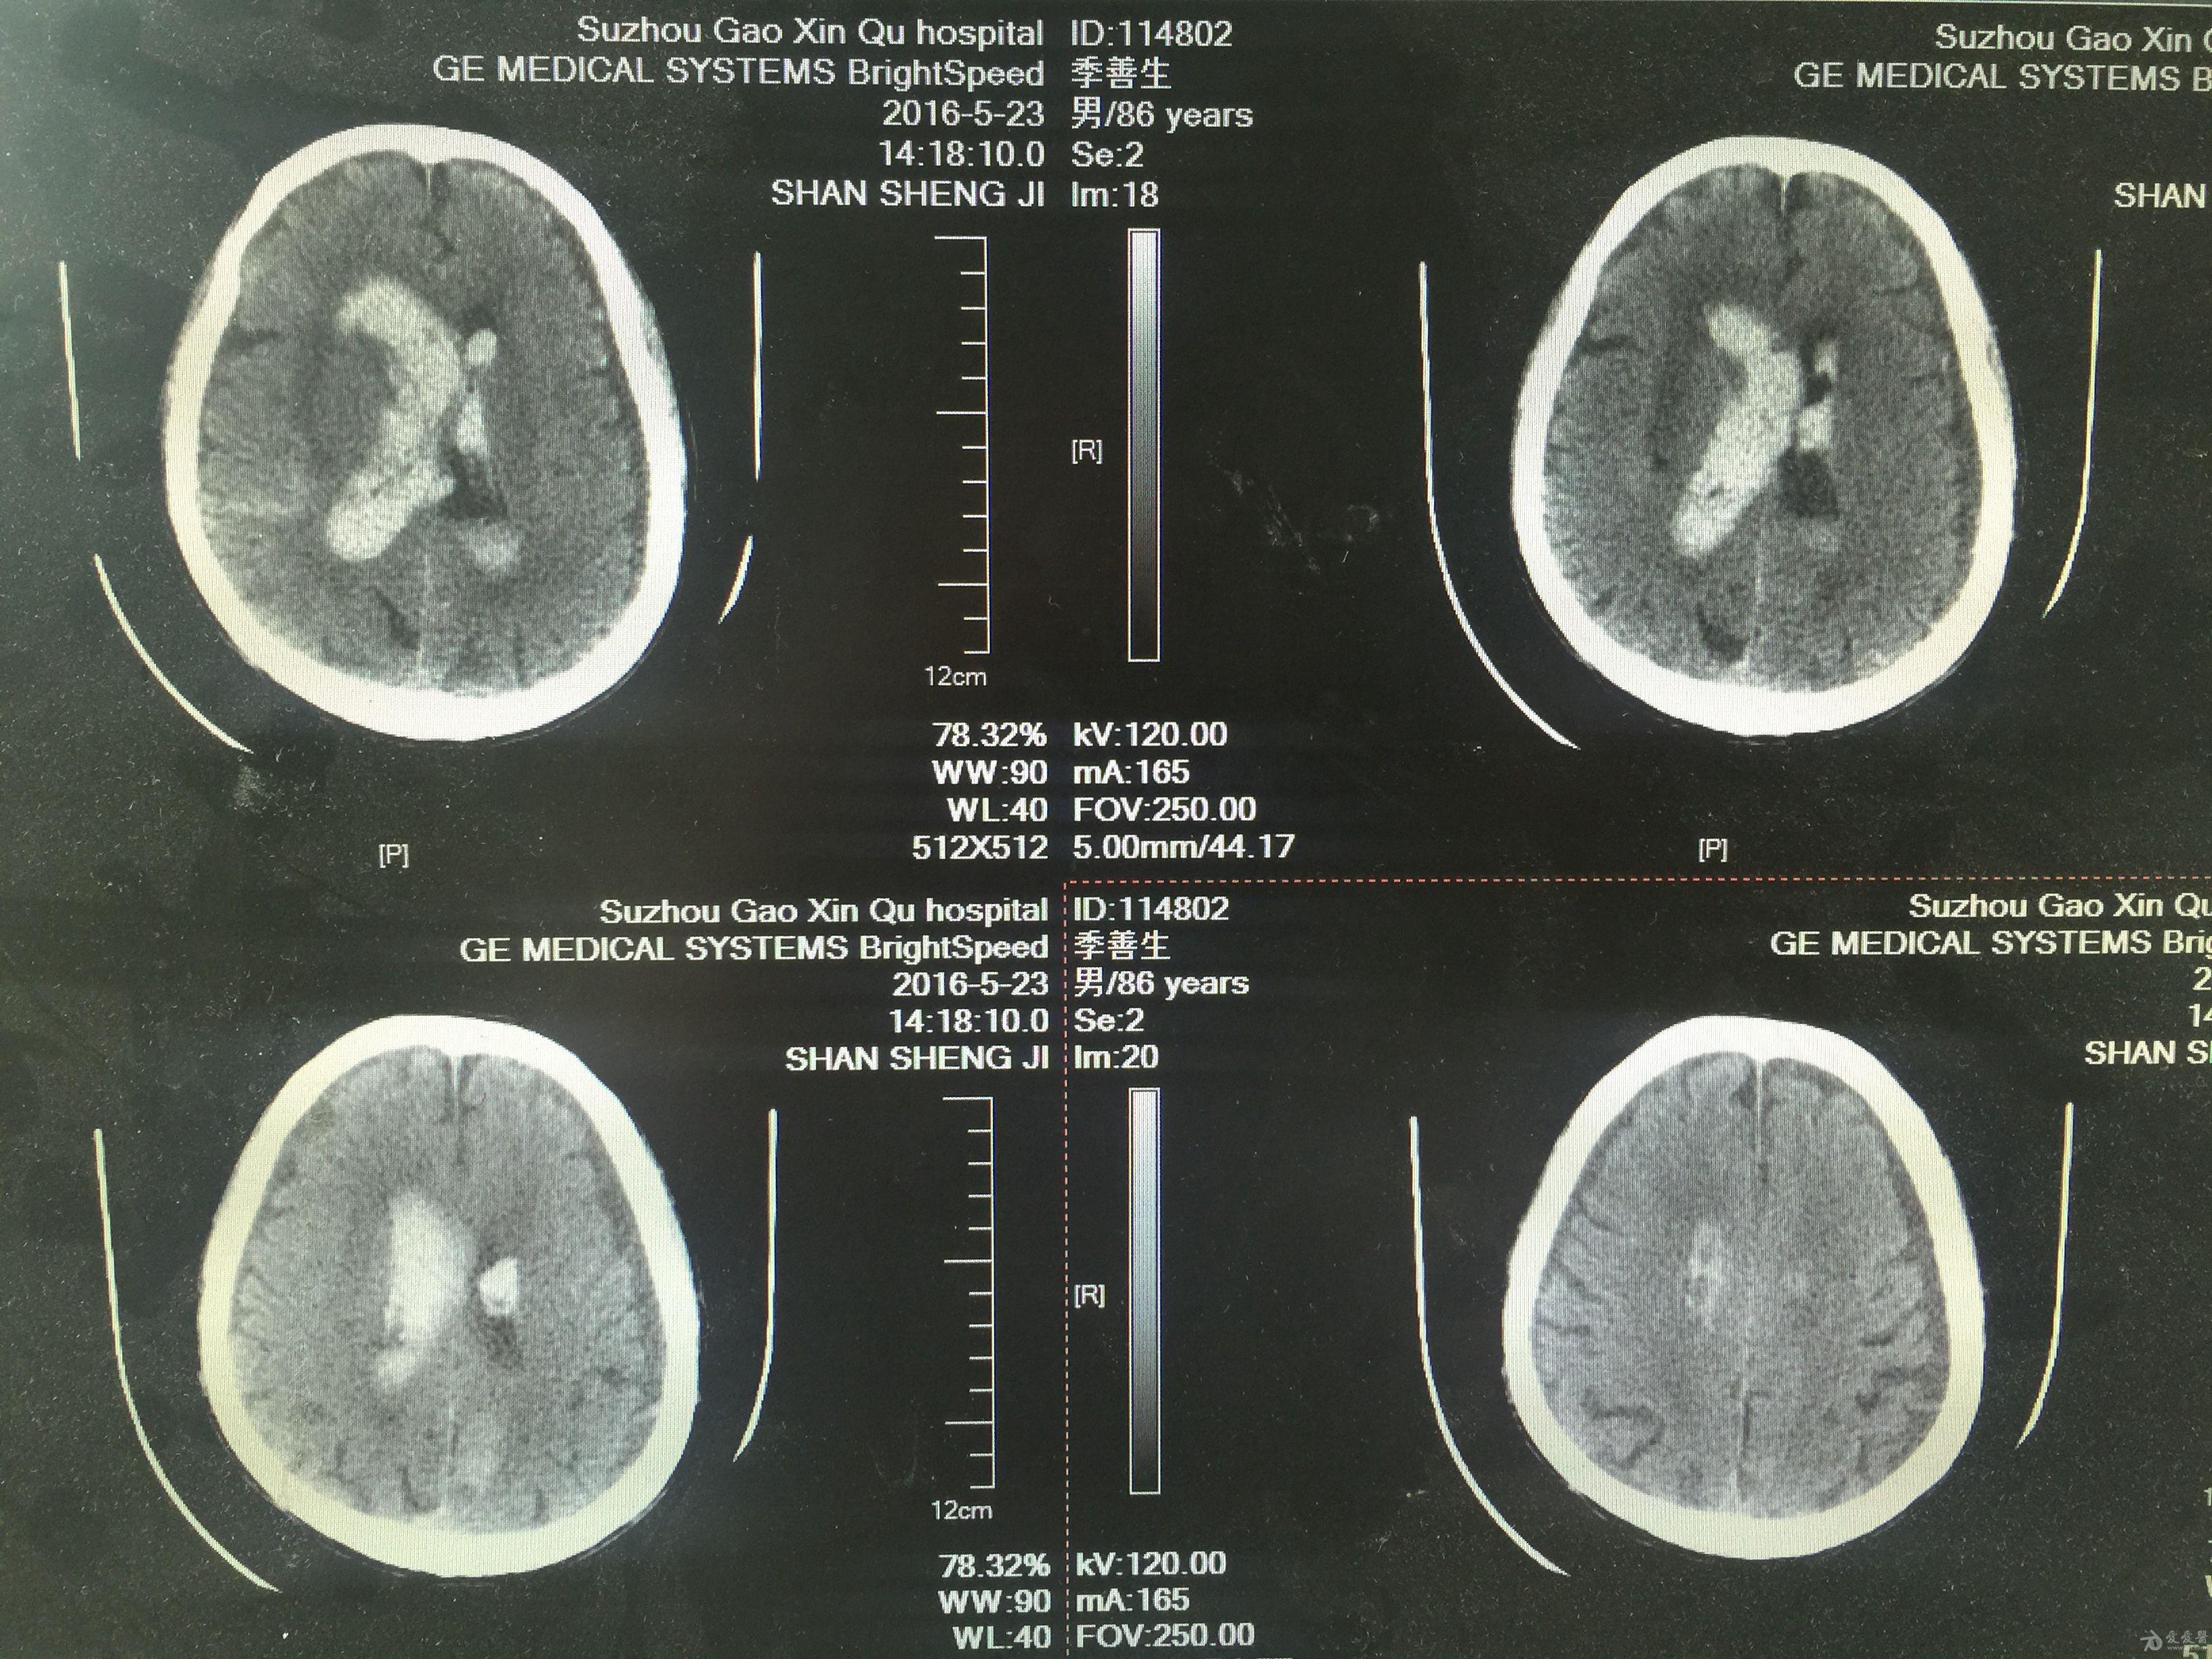

分享一例基底节出血脑室铸型病例(原创) - 神经外科专业讨论版 - 爱爱

图片尺寸3264x2448